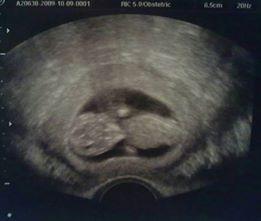

Per Daniela di Un libro per amico"Un'immagine capace di cambiarti la vita. 6.5 centimetri di amore, un cuore che batte in tutta la sua fragilità, una vita che in un attimo ti trasforma da donna a mamma"